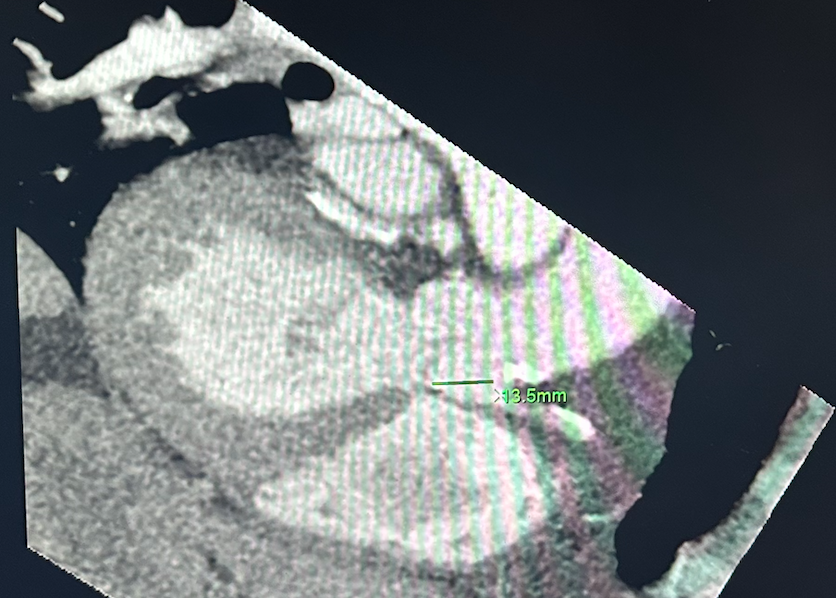

• RCA + Aortic valve in same plane with measurement included (left image)

• Left main + Aortic valve in same plane with measurement included (right image)